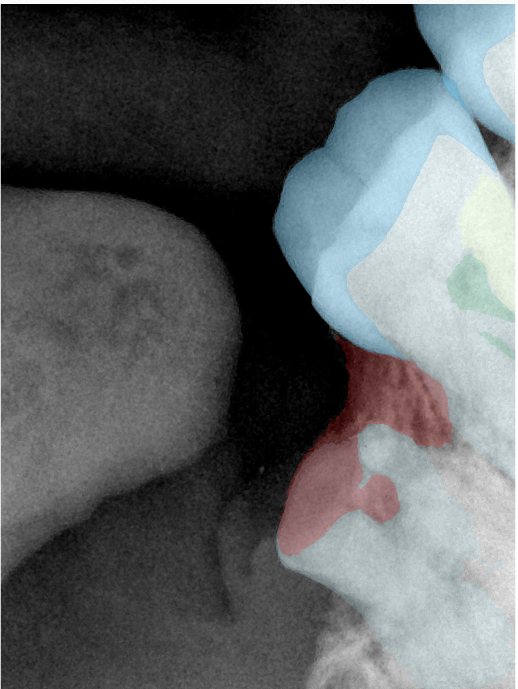

CR/DR 牙齿分割阶段记录

当前进展

- 完成了 CR/DR 牙齿相关分割训练

- 当前结果已经达到阶段预期,但仍有细节问题需要继续处理

相关测试

遇到的问题

- 训练过程中出现过 mask 下移问题

- 部分结果会出现 box 填充异常

- mask 边缘仍然有比较明显的锯齿感

参考

第二版算法问题测试

Updated: 2026-04-13(更新日期)

| 第一版 | 第二版 | 是否解决 | |

|---|---|---|---|

![]() | ![]() ![]() 边角识别有问题 龋齿识别不全 牙髓识别不全 | ![]() | 解决 |

![]() | ![]() 边角识别有问题 识别信息有误 自查(牙冠识别不全) | ![]() | 解决 |

![]() | ![]() ![]() 边角识别有误 大范围填充识别遗漏 | ![]() | 解决 |

![]() | ![]() 识别信息不全 | ![]() | 解决 |

![]() | ![]() ![]() 边角问题 牙胶识别不全 牙冠识别不全 | ![]() | 解决 |

![]() 换图片 | ![]() | ![]() 牙冠部分稍微白了一些就识别成小范围修补,部分判断异常 | 部分解决,修复类略敏感,牙冠部分稍微白了一些就识别成小范围修补,部分判断异常。 |

![]() | ![]() ![]() 牙冠识别不全 牙髓不全 根尖炎龋齿识别有误 | ![]() | 解决 |

![]() | ![]() | ![]() | 解决 |

![]() 换图片 | ![]() | ![]() | 解决 |

![]() | ![]() 牙冠识别有误 | ![]() | 解决 |

![]() 换图片 | ![]() ![]() 边角识别有误 | ![]() 修复类敏感 | 部分解决,图像过白,导致修复类判断异常。 |

![]() 换图片 | ![]() 牙冠识别不全 | ![]() 修复类敏感 | 部分解决,图像过白,导致修复类判断异常 |

结论:修复类出现了不鲁棒的情况,后续需要加入轮廓的扩充数据进行增强。